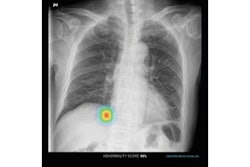

An artificial intelligence (AI) algorithm can catch lung cancers that were initially missed by radiologists on chest radiographs and improve radiologist performance when used as a second reader, according to research published online December 10 in Radiology: Cardiothoracic Imaging.

In testing on an enriched dataset, a team of researchers led by Dr. Ju Gang Nam of Seoul National University Hospital in South Korea found that a commercial deep-learning algorithm yielded significantly higher sensitivity and specificity than four thoracic radiologists. When used by the radiologists as a second reader, the model also significantly improved their detection performance.

Unlike previously reported CAD systems that were shown to yield frequent false-positive findings, the AI software produced significantly higher specificity (p = 0.01) than that of the pooled radiologists, according to the researchers. What's more, the radiologists experienced significantly higher sensitivity (p < 0.001) and specificity (p < 0.01) after they had assistance from the algorithm, according to the researchers.

Left: Image of a 64-year-old woman with confirmed lung adenocarcinoma at the right lower lobe (arrow). Center: The lesion, located at the right retrodiaphragmatic area, was missed during routine clinical practice. Right: In the reader performance test, none of the thoracic radiologists detected the lesion. The algorithm successfully localized the lesion (light blue shaded area) with a probability score of 0.16. Caption and images courtesy of the RSNA.Although their performance improved after using the algorithm, the radiologists could not reach the model's standalone performance level, according to the authors. The readers were likely to miss retrocardiac and retrodiaphragmatic nodules. At lower lung fields, they also neglected more true nodules, regarding them as nipple or vascular shadow, the researchers noted.

"Because the algorithm takes pixel values of the image, it may recognize abnormalities in areas of soft-tissue density better than do human readers," they wrote. "In addition, readers accepted larger nodules and showed limited acceptance rate for subcentimeter nodules."